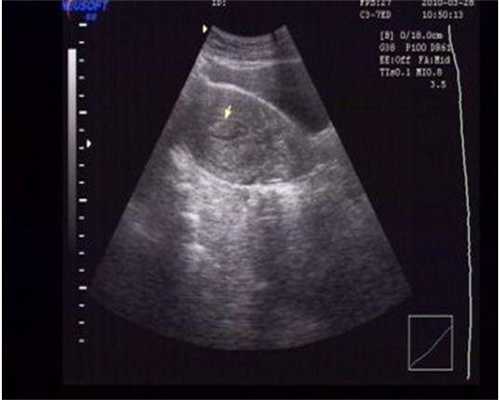

在超声波的引导下,将未成熟的卵泡穿刺,将卵泡液抽出,然后观察患者内分泌功能的变化情况。

超声下卵泡穿刺方法

超声下卵巢打孔的方法有哪些?

超声下的卵巢打孔术,是在静脉麻醉下进行的,因为没有促排卵的卵巢体积较小,活动度大,穿刺小卵泡时卵巢很难固定,穿刺时卵巢游动较大,牵拉感非常不适,所以在麻醉下进行是比较安全的。

超声下卵泡穿刺

医生通常选择18G的取卵针,负压在-120~130mmHg,逐个穿刺小卵泡。对卵巢又厚又韧的表面的小卵泡进行打孔,吸出卵泡液,可以减少雄激素的合成,减轻卵巢环境对卵泡成熟的抑制。